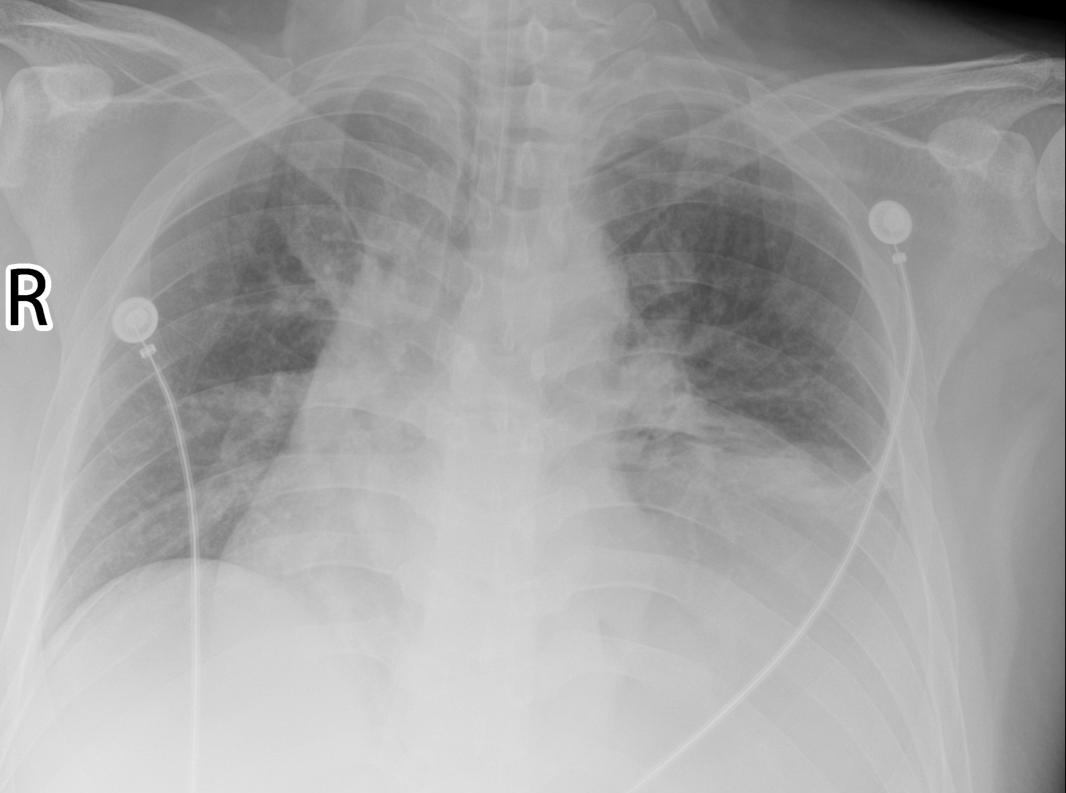

李先生(化名)最初因“发现结肠多发息肉”入院,在日常生活中,他长期感到气短、胸闷,影响其生活质量。为明确病因,心胸外科医生为他进行了全面系统的检查。胸部CT结果显示其左侧膈肌明显膨升,几乎占据半个胸腔,导致纵隔右偏,左肺局部受压膨胀不全,确诊为重度左侧膈膨升。这一病情不仅复杂,也对呼吸和消化功能造成了显著影响。

术后,李先生胸闷、气短等症状明显缓解。复查显示其左侧膈肌位置已显著下降,肺组织复张良好。术后第二天即可下床活动,饮食睡眠改善,伤口愈合良好。